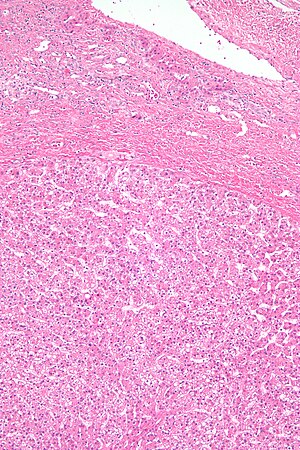

Microscopic

Features:

- Sheets or cords of cells with mild variation of cell and nuclear size.[4]

- Cords of cells up to 3 cells thick.[5]

- Cells may have cytoplasmic clearing due to glycogen or be pale - obvious if seen.

- Vascular - large arteries, dilated thin-walled veins.

Negatives:

- No bile ducts.

- No portal tracts.

- No cirrhosis! If cirrhosis is present it isn't a hepatic adenoma - important.

DDx:

- Well-differentiated hepatocellular carcinoma.[6]

- Hepatic adenoma is differentiated from well-differentiated HCC by its architecture; adenomas have cords of cells upto 3 cells thick & have preserved reticulin architecture.

- Focal nodular hyperplasia.